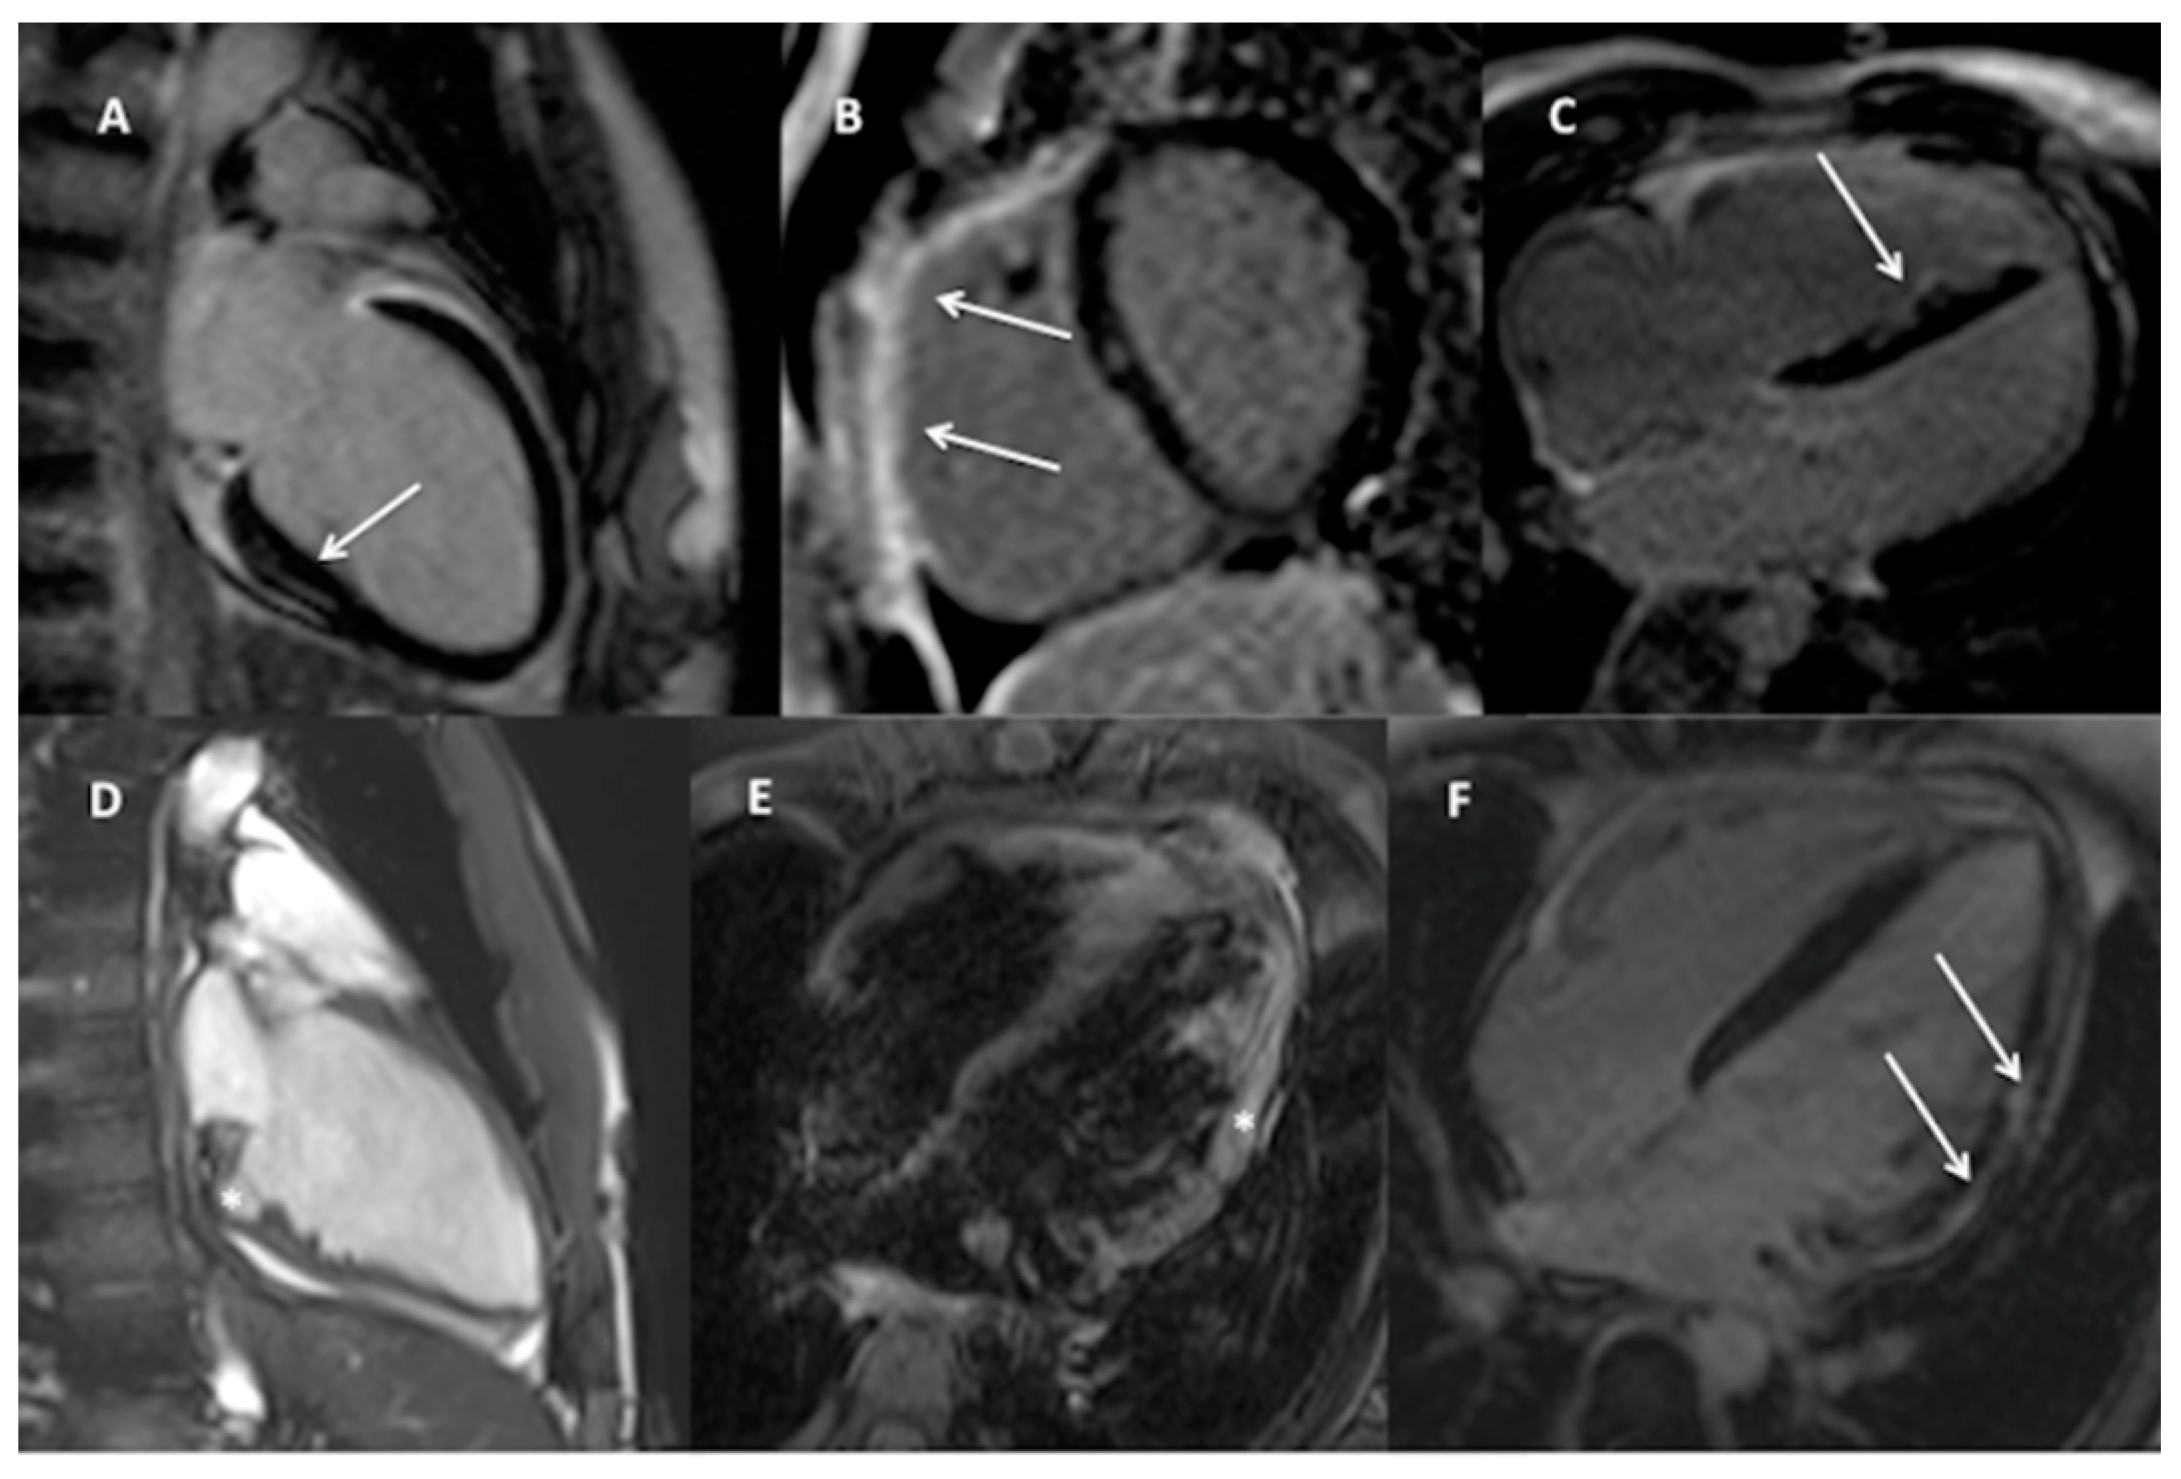

3.2. CMR Findings